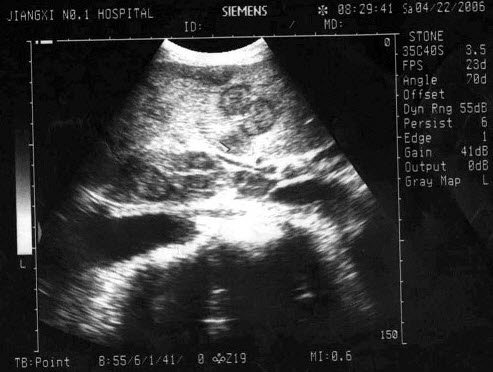

241、单项选择题

男,60岁,上腹疼痛不适数10年。结合超声声像图,诊断为()

A.胆囊多发性结石

B.胆囊多发性息肉

C.胆囊泥沙样结石

D.胆囊充满性结石并萎缩性胆囊炎

E.胆囊胆固醇结晶